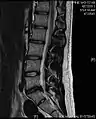

Narrowed space between L5 and S1 vertebrae, indicating probable prolapsed intervertebral disc – a classic picture

- Magnetic resonance imaging is the gold standard study for confirming a suspected LDH. With a diagnostic accuracy of 97%, it is the most sensitive study to visualize a herniated disc due to its significant ability in soft tissue visualization. MRI also has higher inter-observer reliability than other imaging modalities. It suggests disc herniation when it shows an increased T2-weighted signal at the posterior 10% of the disc. Degenerative disc diseases have shown a correlation with Modic type 1 changes. When evaluating for postoperative lumbar radiculopathies, the recommendation is that the MRI is performed with contrast unless otherwise contraindicated. MRI is more effective than CT in distinguishing inflammatory, malignant, or inflammatory etiologies of LDH. It is indicated relatively early in the course of evaluation (<8 weeks) when the patient presents with relative indications like significant pain, neurological motor deficits, and cauda equina syndrome. Diffusion tensor imaging is a type of MRI sequence used for detecting microstructural changes in the nerve root. It may be beneficial in understanding the changes that occur after herniated lumbar disc compresses a nerve root, and might help in differentiating the patients that need surgical intervention. In patients with a high suspicion of radiculopathy due to lumbar disc herniation, yet the MRI is equivocal or negative, nerve conduction studies are indicated.[44] T2-weighted images allow for clear visualization of protruded disc material in the spinal canal.

MRI scan of large herniation (on the right) of the disc between L4 and L5 vertebrae

A rather severe herniation of the L4–L5 disc

Example of a herniated disc at L5–S1 in the lumbar spine